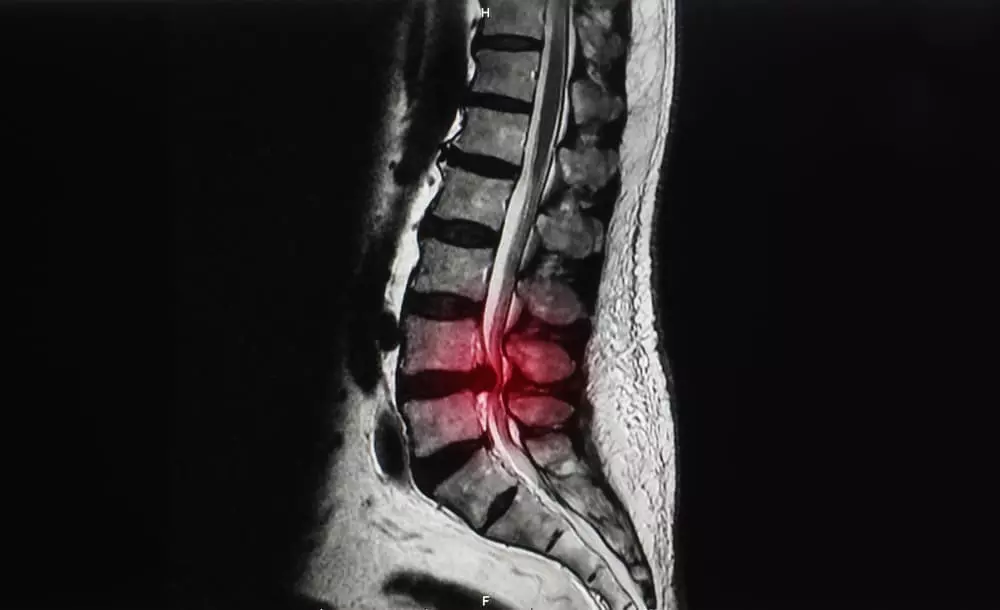

脊柱管狭窄症とは?

脊柱管狭窄症

脊柱管狭窄症って

いったいどんなもの?

背骨は、32から34個の椎骨が連なってできています。

その中には空洞があり、脊髄や血管が通る脊柱管と呼ばれる通路があります。

この脊柱管が何らかの理由で狭くなり、神経を圧迫することで、痛みやしびれといった症状が現れるのが脊柱管狭窄症です。